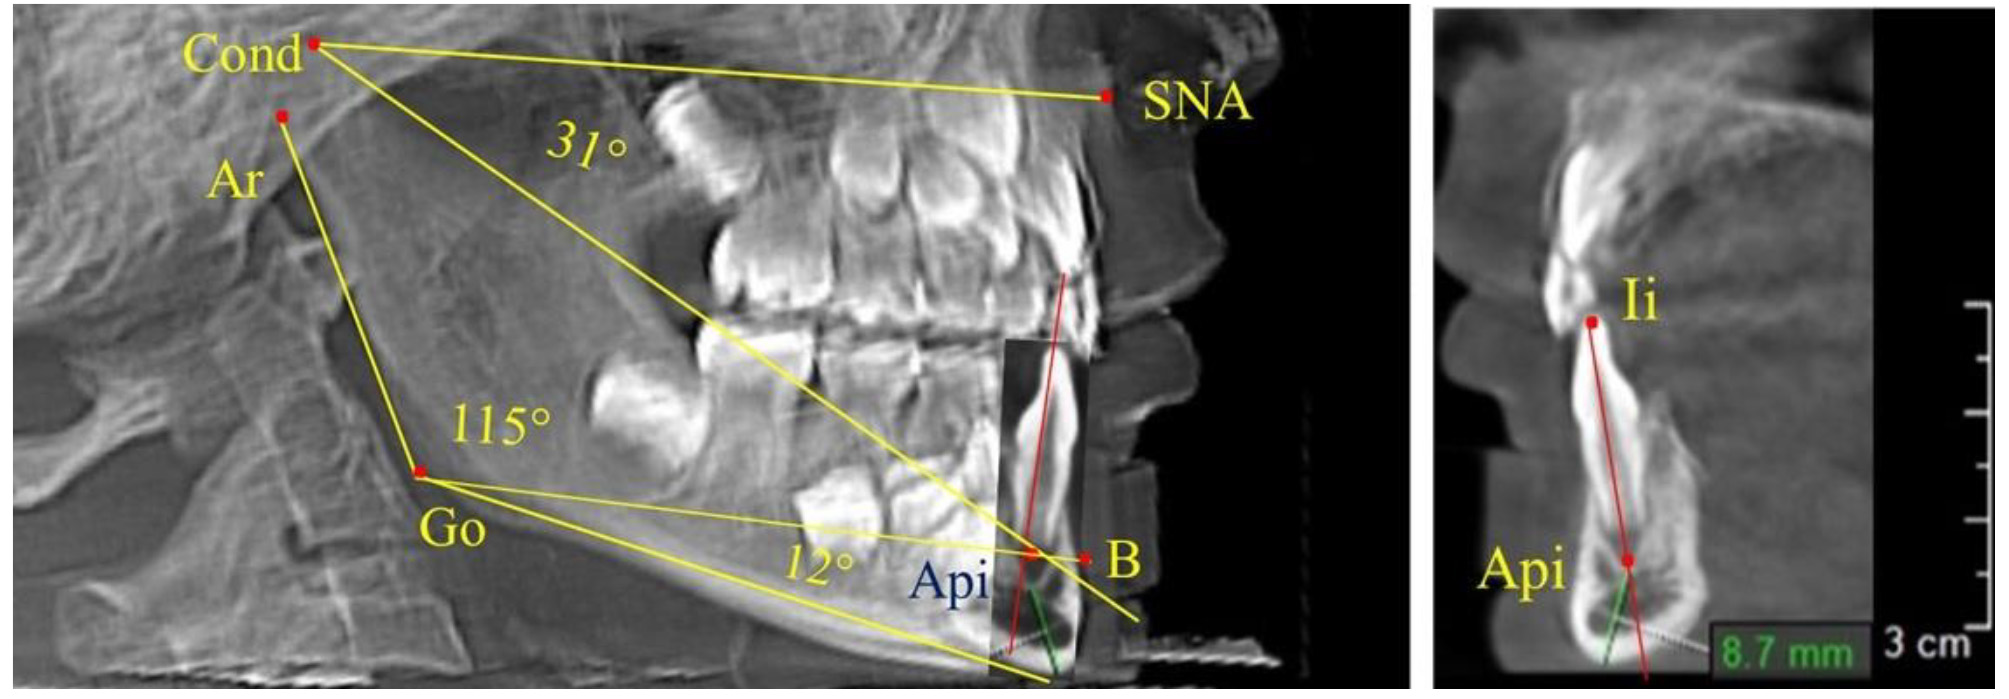

Особенность анализа телерентгенограммы в периоде сменного прикуса заключалась в том, что наслоение зачатков постоянных зубов затрудняло определение апикальной точки нижнего резца. В подобных случаях использовали метод совмещенного анализа телерентгенограммы с фрагментом томограммы, на котором, также как и на телерентгенограмме, определяли положение резцовой и апикальной точек с построением условной вертикали, которая служила ориентиром для совмещения фрагментов (рис. 2).

Рис. 2. Особенности совмещения телерентгенограммы с фрагментом томограммы в сменном прикусе

При анализе ТРГ 5 детей в периоде прикуса молочных зубов отмечено, что величина основного угла гнатической части лица SNA-Cond-Api, как правило, в норме составляла около 30°, и его величина была относительно стабильной у всех обследованных детей. В то же время угол нижней челюсти и его составляющие отличались вариабельностью параметров при различных показателях нижнечелюстного угла (рис. 4).

Рис. 4. Особенности ТРГ (а) и 3D-модели (б) в периоде прикуса молочных зубов

Таким образом, в периоде молочного прикуса с оптимальными окклюзионными соотношениями, несмотря на линейные размеры в вертикальном и сагиттальном направлении, которые, безусловно, меньше параметров взрослых людей, величина основного угла гнатической части лица SNA-Cond-Api соответствовала параметрам людей с полностью сформированным физиологическим прикусом постоянных зубов. Анализируя данные рентгенограмм детей в периоде сменного прикуса, отмечено, что величина основного угла гнатической части лица SNA-Cond-Api, так же как в молочном и постоянном прикусе, в норме составляла от 28 до 32°. В то же время угол нижней челюсти и его составляющие отличались вариабельностью параметров при различных показателях нижнечелюстного угла. Достоверных различий угла гнатической части после смены нижних медиальных резцов и прорезывания первых постоянных моляров (4 ребенка) не было; происходил очередной этап подъема высоты прикуса и увеличение линейных размеров костей гнатической части, однако угловые параметры были относительно стабильны. После смены всех резцов и замены первых молочных моляров первыми премолярами (6 человек) увеличивались линейные размеры при сохранившихся угловых показателях гнатической части лица (рис. 5).